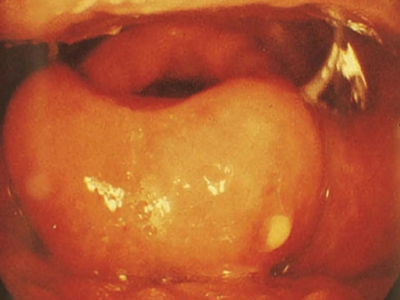

急性会厌炎是会厌及周围软组织的迅速肿胀,并可引起致命的呼吸道突然阻塞。又称为急性声门上喉炎,是会厌的急性感染,炎症发生部位以会厌为主,可向杓会厌襞以及声门上区蔓延。成人及儿童均可发病,但以成人较多见,男性多于女性,常发生于早春与秋末。

急性会厌炎起病急骤,有畏寒、发热、头痛等全身不适,多数患者体温在38-39℃。以剧烈的咽喉疼痛为主要症状,吞咽时加剧,重者饮水呛咳、流涎。喉镜下可见会厌舌面黏膜充血,高度肿胀水肿呈圆球状如卷曲香肠,肿胀可偏于一侧,偶见有黏膜溃疡。